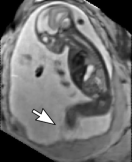

Reconstruction of Fetal Organs: Exemplary PVR and SVR reconstructions under motion introduced by kicking of the fetus are shown in Fig. 11. PVR reconstruction results show an improved visual appearance and less blurring in the region with severe motion artifacts (arrow). An example of a challenging clinical case with a kidney malformation in one of twin fetuses, is shown in Fig. 8. Our clinical partners confirmed that such complications are easier to examine and to quantify after PVR-based reconstruction.